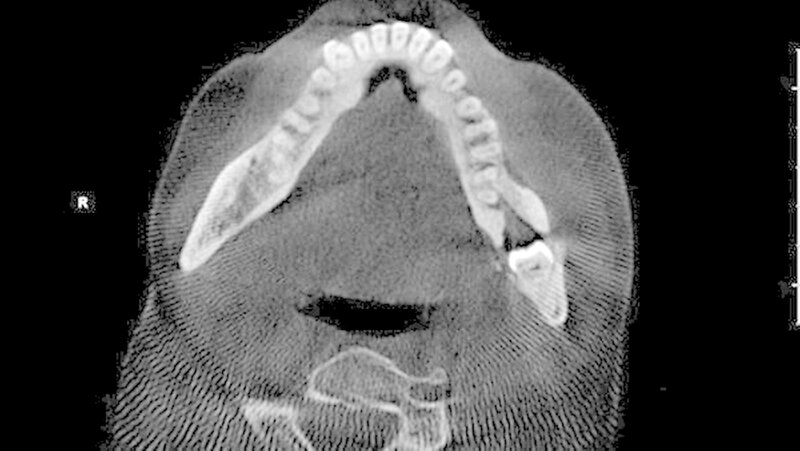

Es erfolgte durch den Hauszahnarzt zunächst eine intraorale Inzision von vestibulär sowie der Beginn einer oralen Antibiotikatherapie mittels Clindamycin 300 mg 1-1-1. Unter regredienter Symptomatik wurde die Patientin zur weiteren Therapie überwiesen. Nach ausführlicher Anamnese und klinischer Untersuchung wurde die Röntgendiagnostik durch eine Digitale Volumentomografie (DVT) zwecks exakter Lagebestimmung des retinierten Zahns 38 erweitert. Das DVT war insbesondere im Hinblick auf die anatomische Lagebeziehung zum Nervus alveolaris inferior aber auch zur Evaluation der Osteodestruktion nach stattgehabtem Entzündungsgeschehen indiziert.

Hierbei kam der Zahn 38 in seiner Längsachse rund 6 mm parallel zum Unterrand der Mandibula im Bereich des linken Kieferwinkels zur Darstellung. Weiterhin fiel eine perikoronare Transluzenz und die enge räumliche Lagebeziehung zum N. alveolaris inferior auf. Im weiteren Verlauf wurde die Indikation zur operativen Entfernung des Zahns von extraoral gestellt. Die Indikation zu diesem Eingriff war in der Sanierung des Infektionsherdes und damit der Prävention einer erneuten Entzündung und weiterer osteolytischen Schädigung des Unterkiefers begründet.